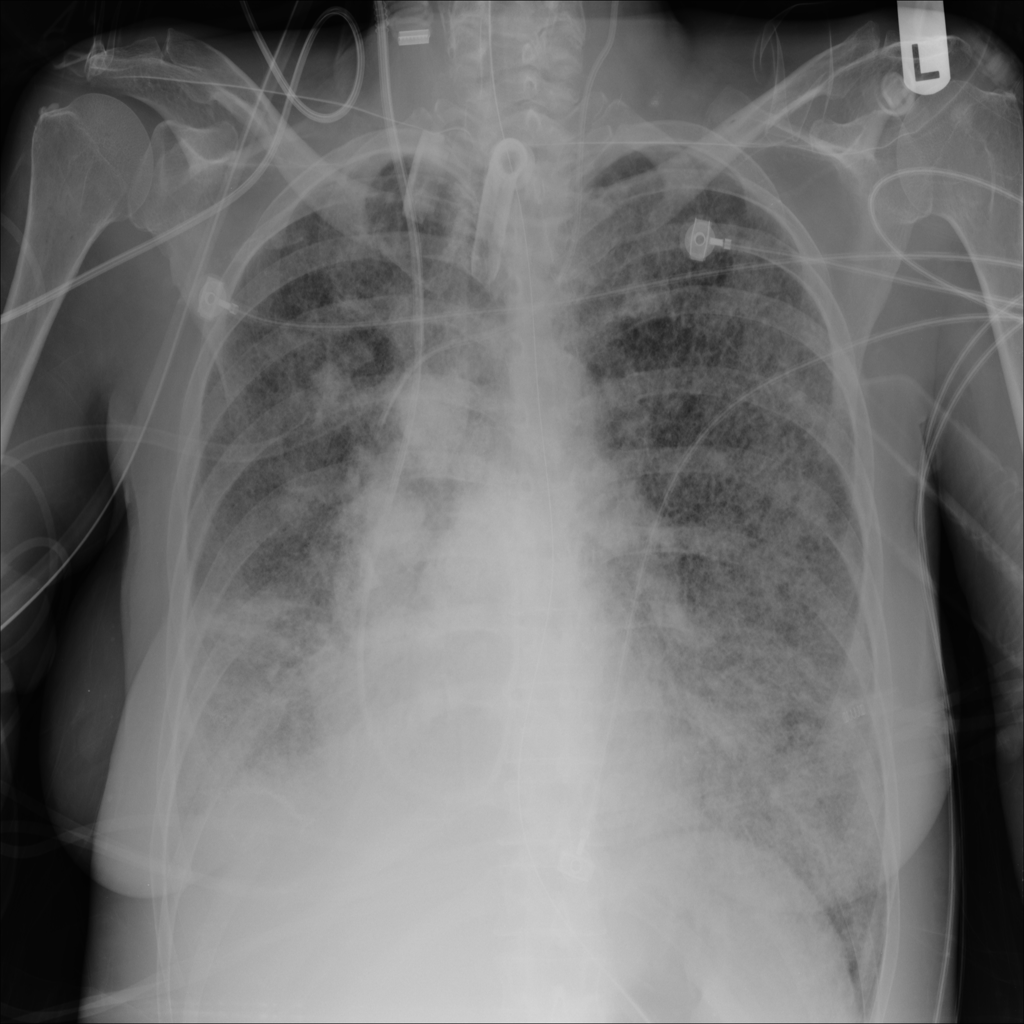

Mass

A mass is a larger focal opacity or lesion seen on the image. It is a descriptive finding that can have several causes and usually needs more imaging or clinical context to characterize.

PAT-50E5 · IMG-008Mass

PAT-50E5 · IMG-008

PA